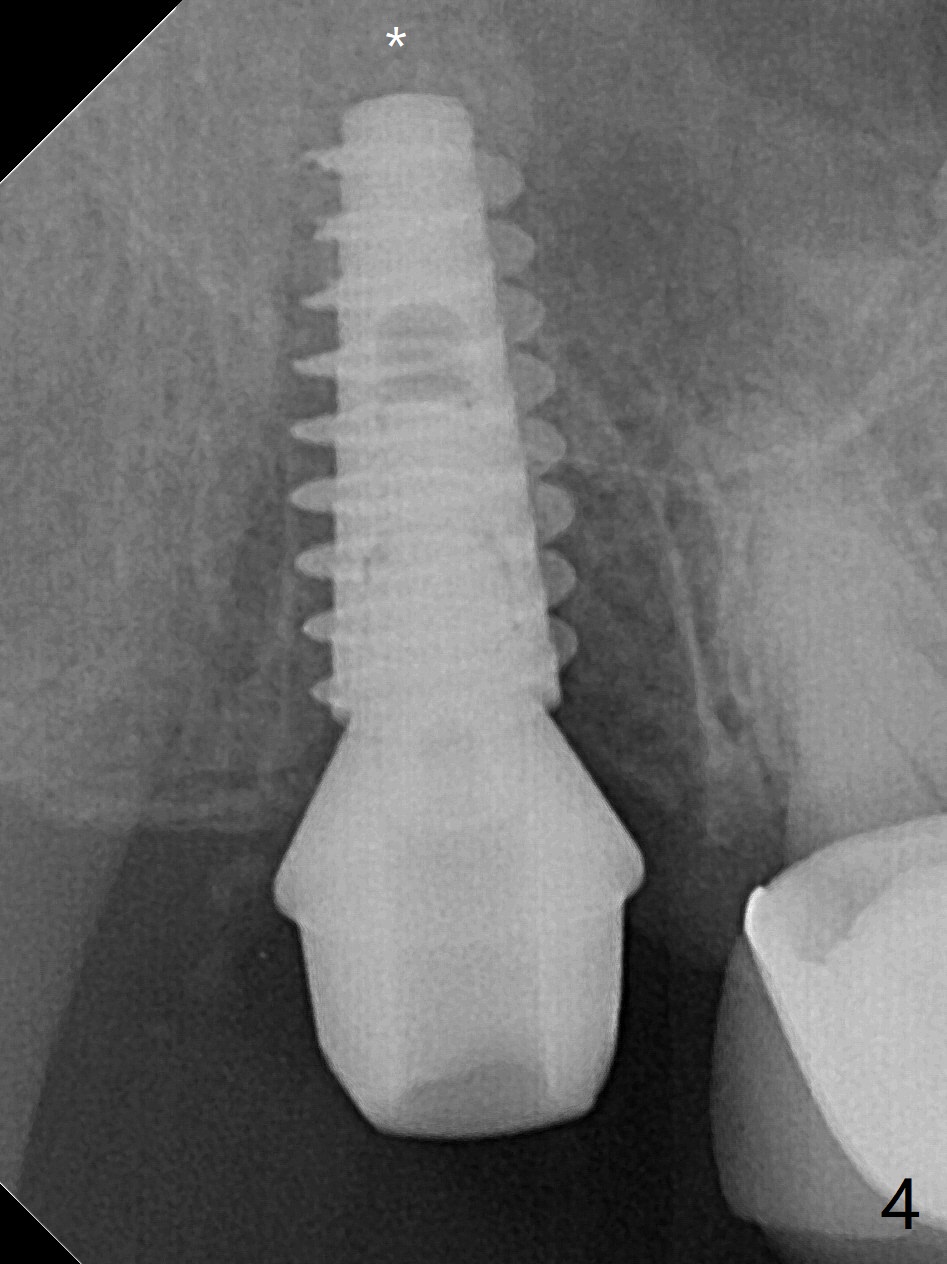

When the tooth #2 is extracted, there is sinus perforation in the palatal apex, consistent with preop CT (Fig.1: P). There is no bone shaving associated with drill sequence in the buccal socket (until 3.5x8.5 mm). With sticky bone and 4.5x10 mm IS dummy implant, sinus lift does not happen. Sinus floor perforation is felt when a 2.2x10 mm drill is used slowly. But air leaks from the palatal socket. With bone graft, a 4x10 mm dummy implant lifts the sinus (Fig.2). After further graft and 4.5x10 mm dummy implant, a 5x11 mm final implant is placed with 15 Ncm with sinus lift (Fig.3,4 *). Following abutment insertion, sticky bone is packed around the implant and abutment (Fig.5,6 S). Prior to final implant placement, a small piece of PRF and collagen and Osteogen Plugs are placed in the palatal socket for repair. Before discharge, there is mild nasal hemorrhage.